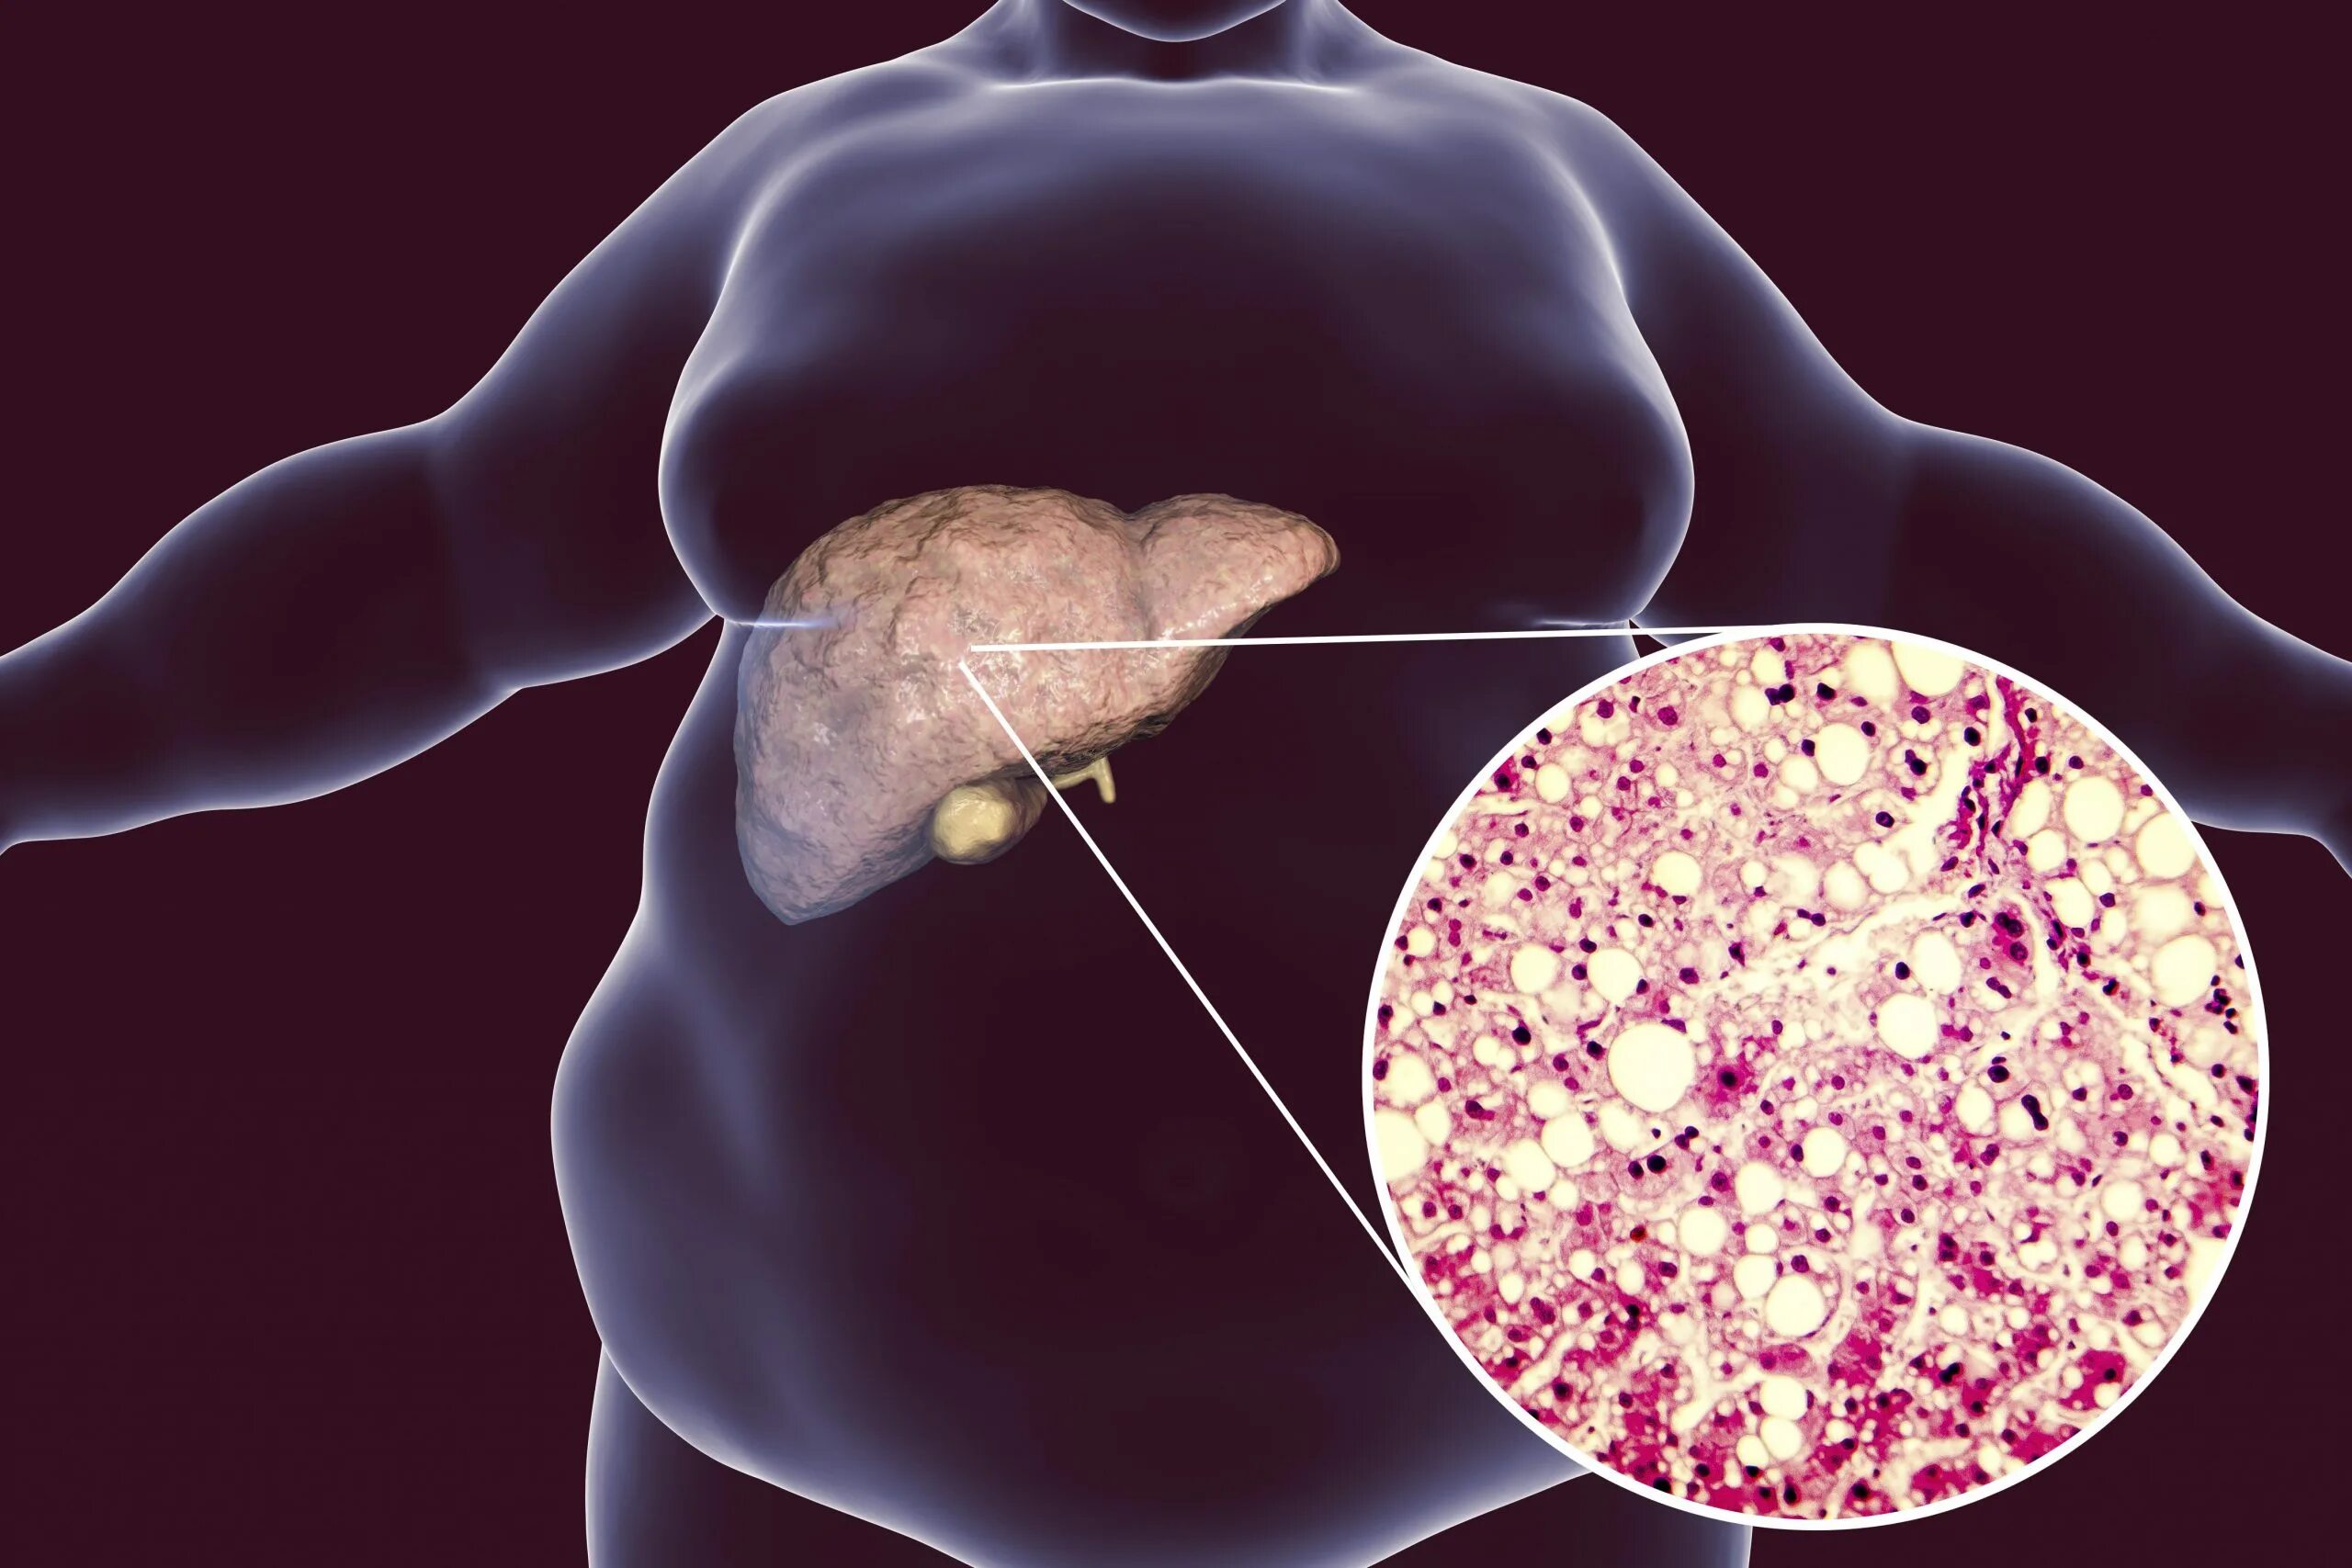

Липидоз печени